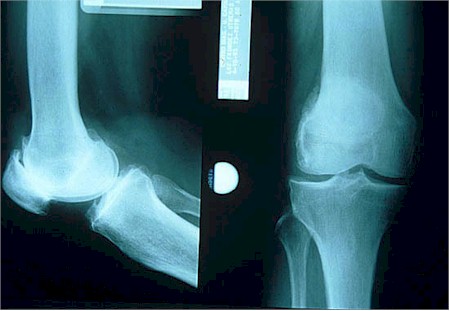

RADIOLOGIA

RX.-Espacio articular disminuido, osteofitos, quistes óseos subcondrales, ausencia de osteoporosis